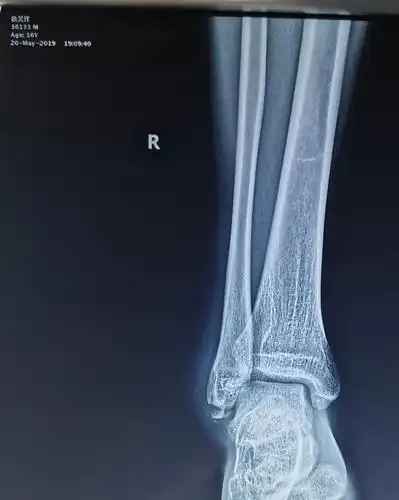

右侧胫腓骨下段骨折

三例胫腓骨远端骨折

胫腓骨骨折全记录